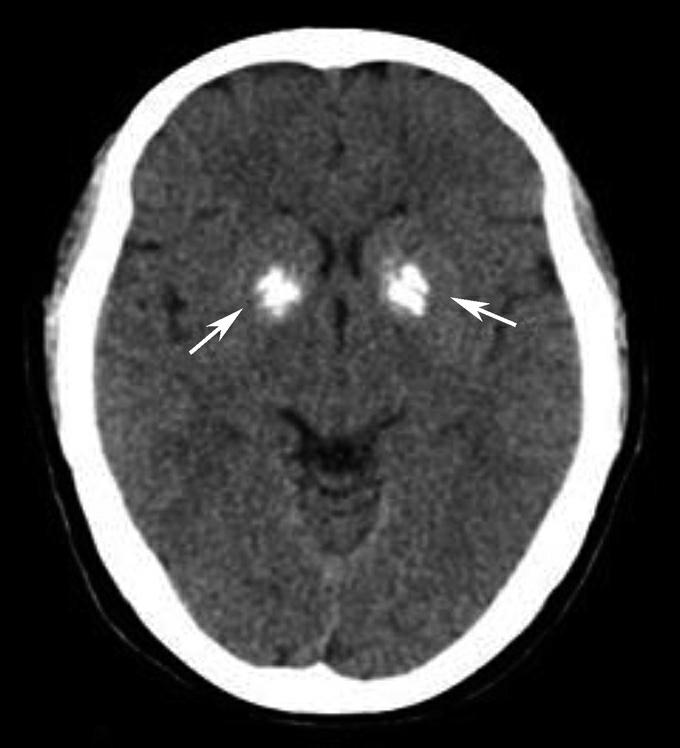

40岁以上正常人可出现基底节钙化,通常双侧对称,也可不对称,以苍白球钙化最为常见。如果30岁以下出现基底节钙化,应警惕病理性钙化。基底节病理性钙化主要为代谢性或内分泌性疾病所致(图1-2-77)。一侧基底节钙化时需注意与脑出血鉴别。

图1-2-77 双侧基底节病理性钙化

女,31岁,甲状旁腺机能减退。双侧基底节见大片钙化(箭)